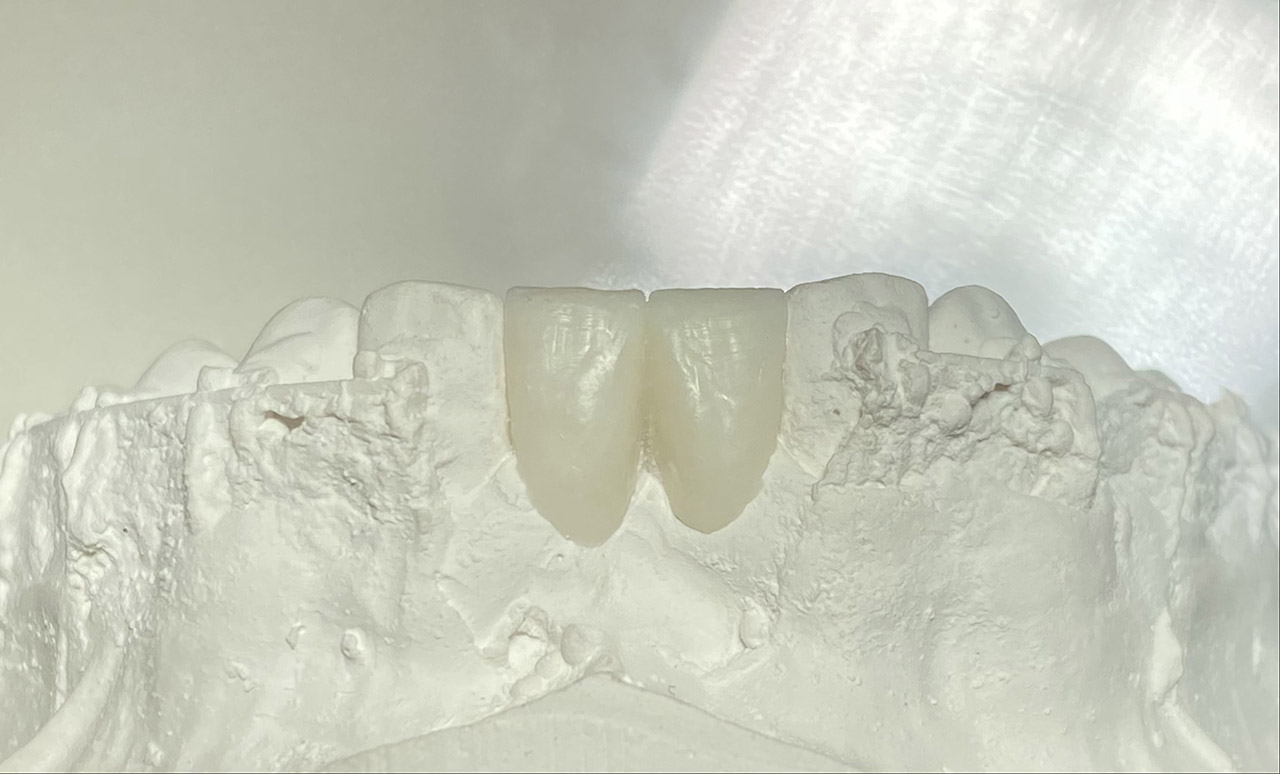

Klebebrücken bei Zahnaplasie (Nichtanlage):

Vorbehandlung (Dr. Ernst Köle): Kieferorthopädischer ”Platzhalter mit provisorischem Zahn”.

Minimalinvasive Therapie: 2 keramikverblendete Klebebrücken (“Zirkonflügerl") adhäsiv zementiert.

Konservativ ohne Knochenaufbau und Schleimhauttransplantat.